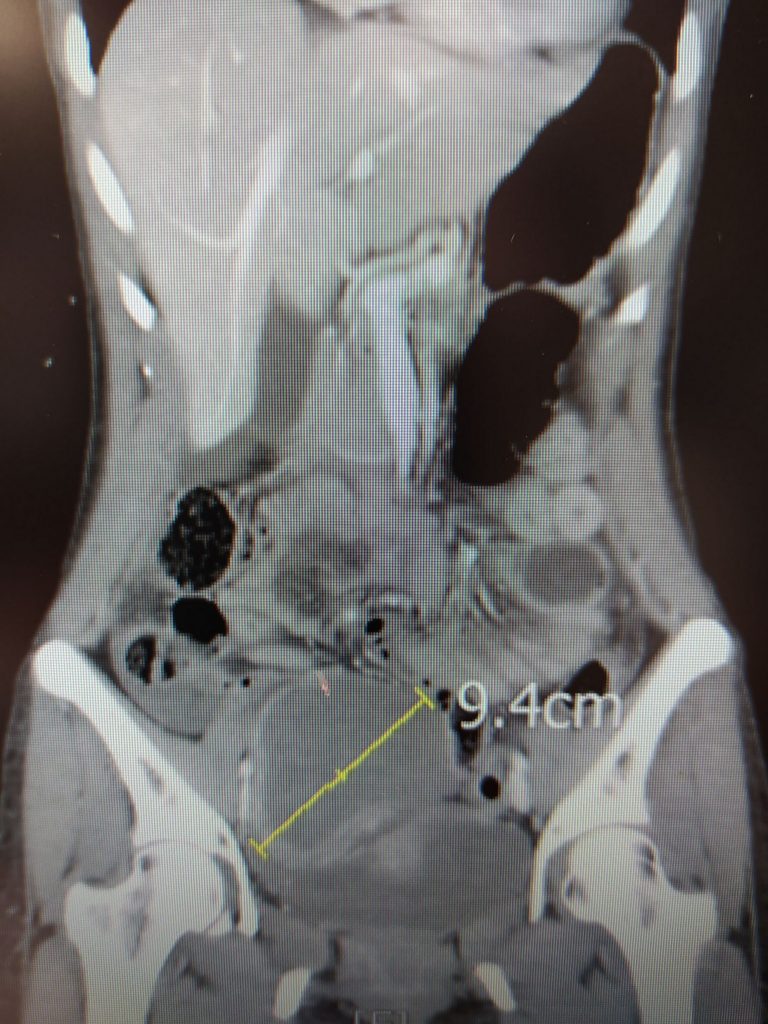

35歲婦人下腹疼痛到冒冷汗,送到臺中慈濟醫院急診就醫。醫師看斷層影像發現竟然是右側卵巢10公分,像顆大蘋果的巧克力囊腫破裂,引發急性腹膜炎。想不到禍不單行,住院前採檢又確診新冠肺炎,婦產科醫師全副武裝在負壓隔離手術室用腹腔鏡順利摘除病灶。

婦人表示,往常經期都沒有特別感覺,今年初起卻每次經期都疼痛不已,在他院就醫服藥幾個月後,右腹竟明顯突出,五月底更劇痛到全身冷汗,直接被送到急診就醫。婦產科醫師黃閔暄從電腦斷層影像發現,劇痛病因來自右側卵巢巧克力囊腫破裂,引發急性腹膜炎,屬於不能再等的急症。即使婦人確診感染新冠肺炎病毒,仍緊急安排病人進入負壓隔離病房,醫療團隊全副武裝在負壓隔離手術室開刀,順利用腹腔鏡摘除形狀有如一顆大蘋果的10公分病灶。